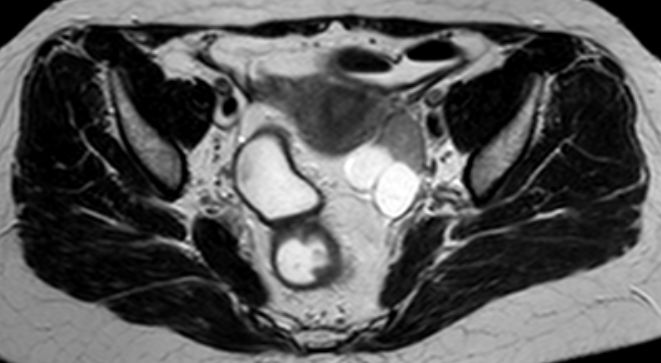

73-jährige Frau mit Ascites, Pleuraerguss links und Unterbauchtumor.  Das Netz ist komplett in einen Omental-Cake umgewandelt. An der Zwerchfellkuppe miliare Tumoraussaat.

Beide Adnexe in knapp kindskopfgroße blumenkohlartige Tumoren umgewandelt.

Im Douglas finden sich pararektal mehrere bis zu pflaumengroße Tumorknoten.